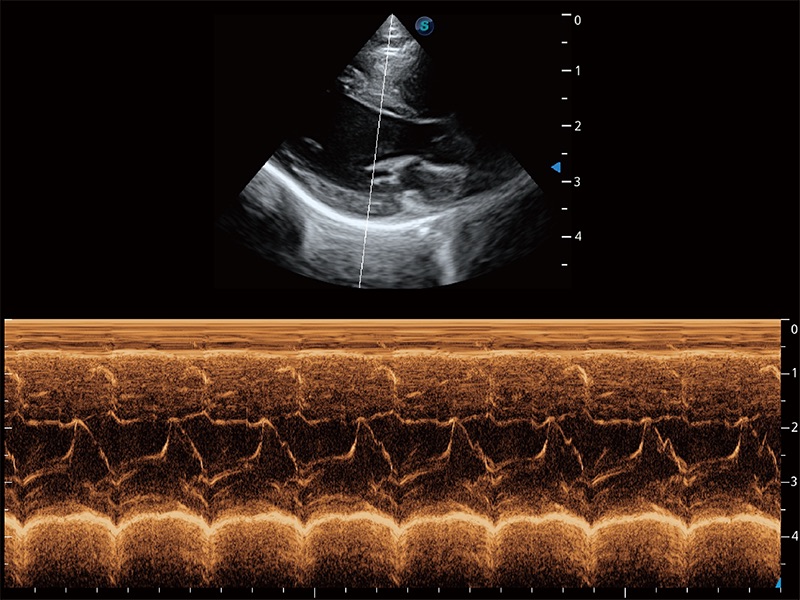

• AMM 解剖M型

通过360度任意调节3条M型取样线,在同一心动周期上观察心脏不同位置的运动曲线,得到准确的心功能测量数据,有效评估心肌运动及左心室功能。

(猫)二尖瓣M型

(犬)二腔心血流